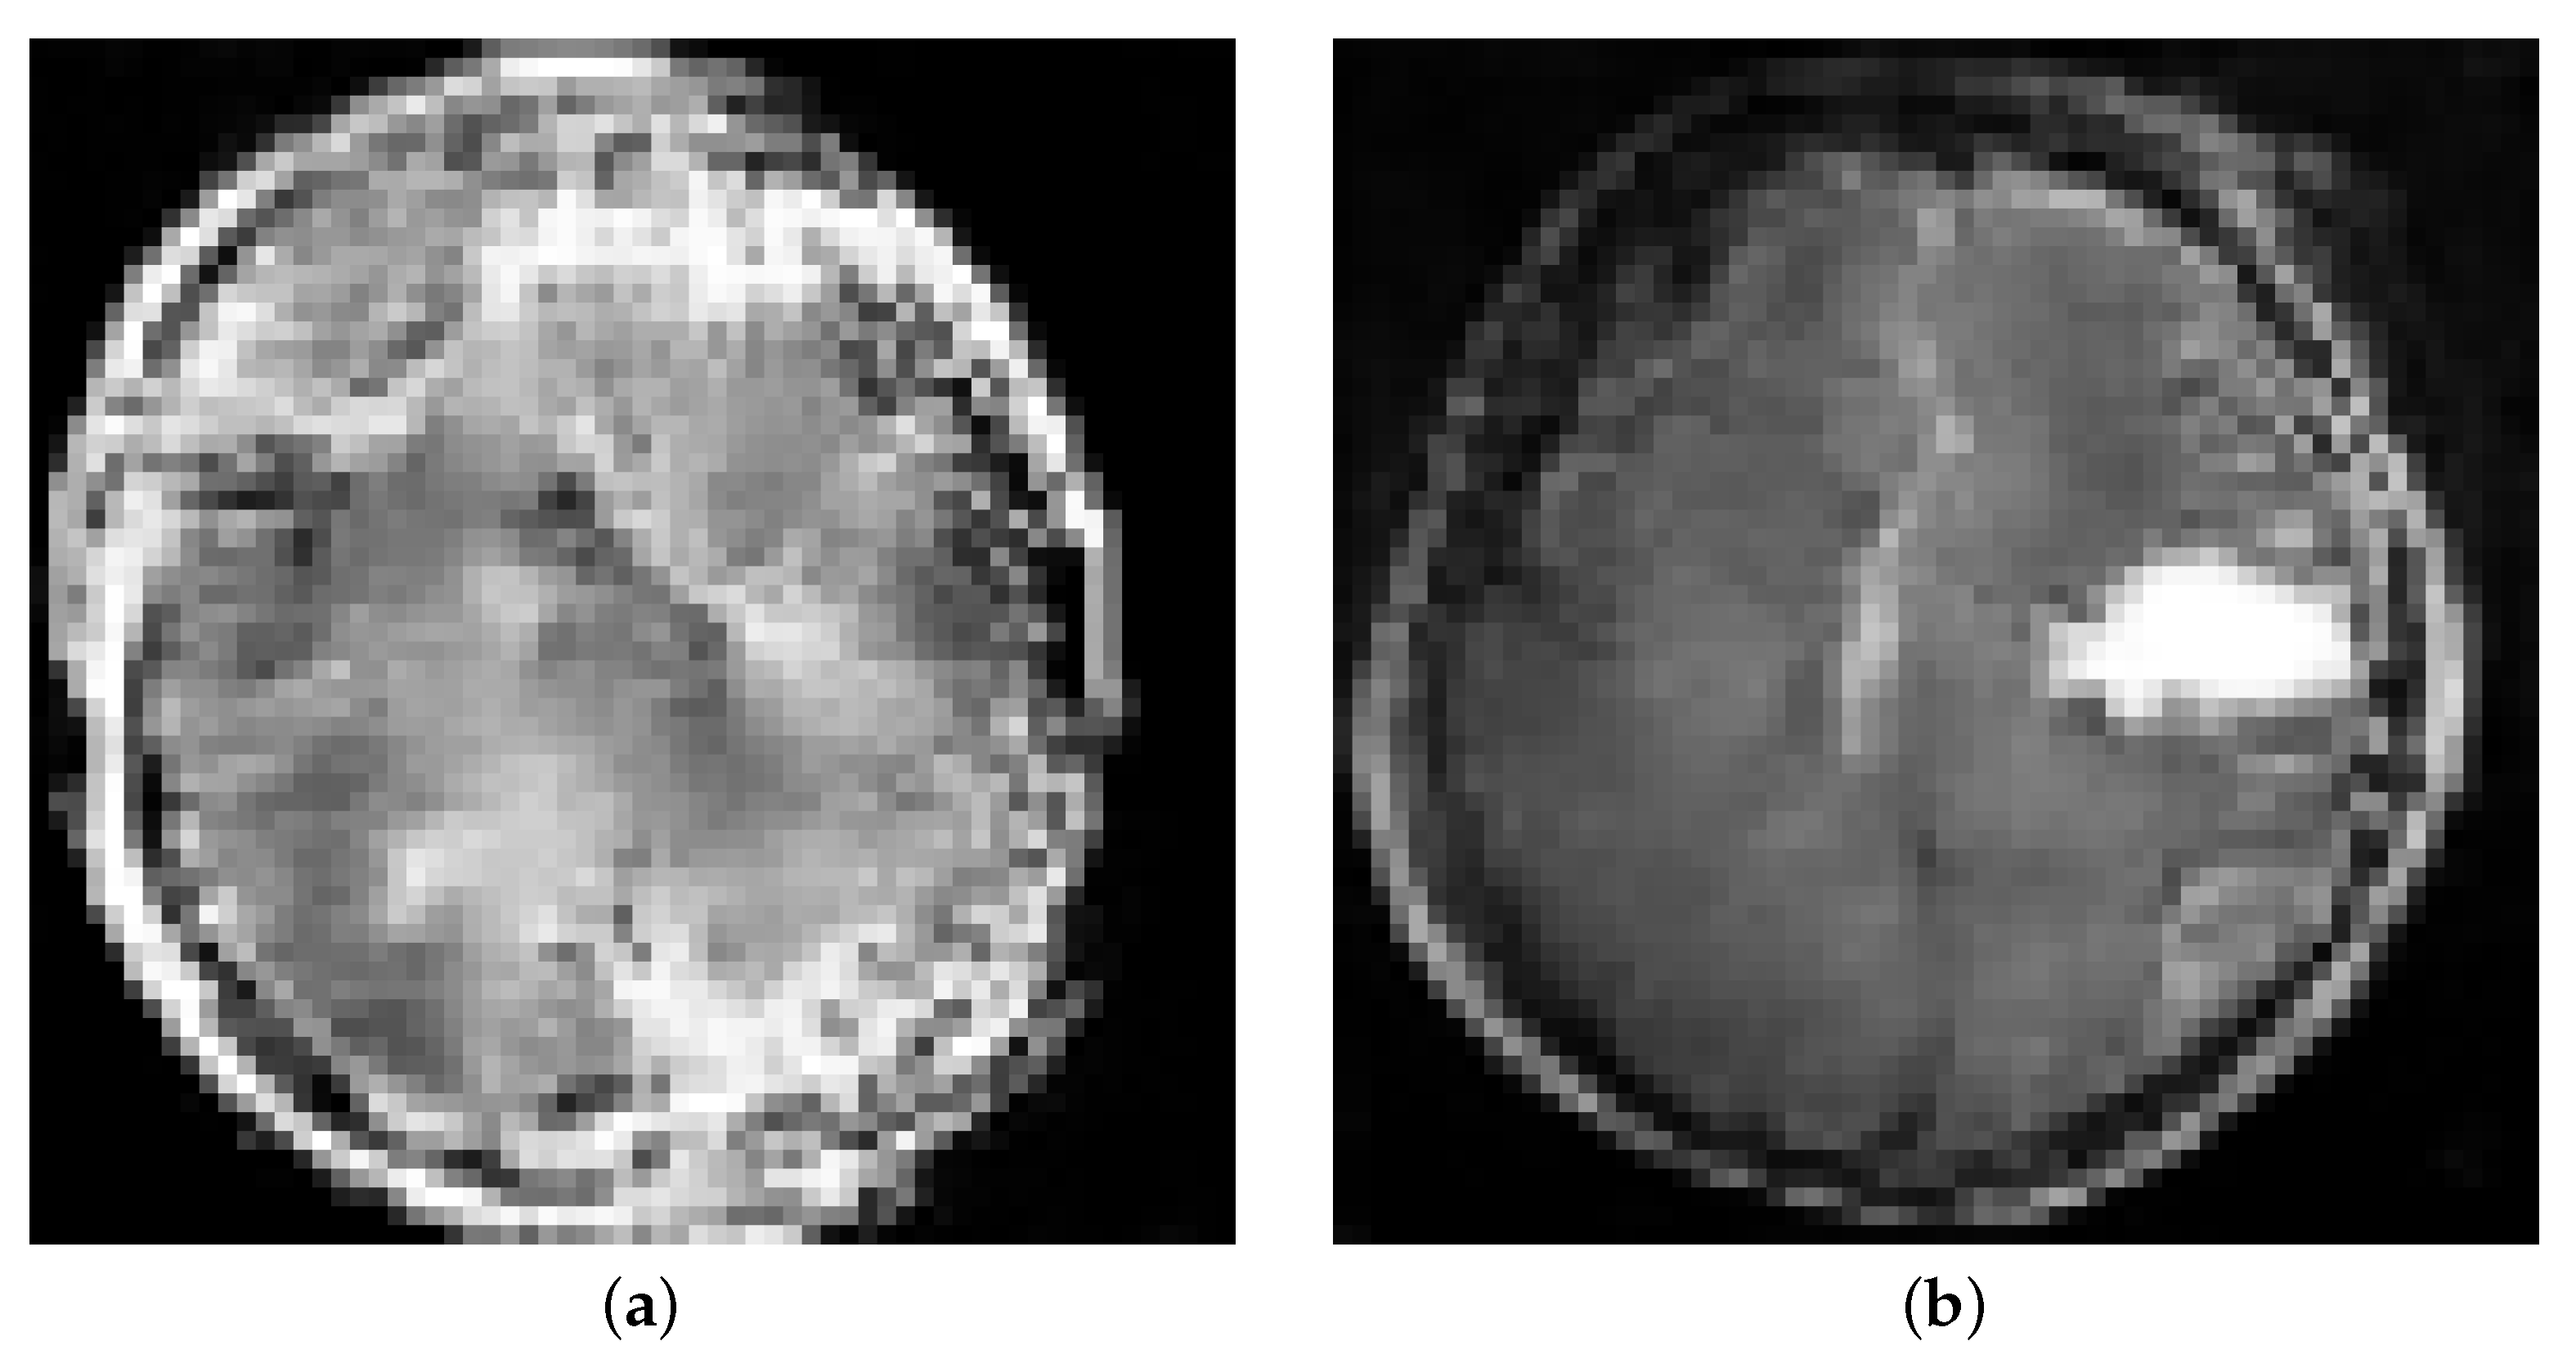

3.5. Data Division and Training of the Models

Figure 2. GAN output using 1000 training datasets at the following epochs: (a) 1 epoch; (b) 100 epochs.